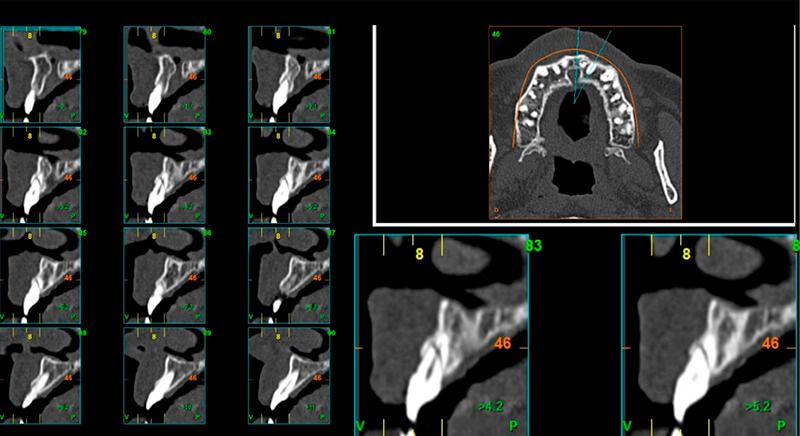

As result of an exhaustive examination a fracture of tooth 1.1 was detected, and although at first a fracture of 2.1 was not observed, it did present movement. Finally, the CT images revealed a radicular apical fracture of tooth 2.1 that meant the tooth could not be saved.

During the digital planning for the implant, with Implant Studio (3Shape) guided surgery software, significant bone defects due to the patient's anatomy were discovered. Placing the implant in the correct position for the prosthesis presented bone dehiscence in the vestibular area, and another bone defect in the palatine area due to the patient's large nasopalatine canal.

This information enabled us to rule out the option of surgery without a flap, as regeneration simultaneous to surgery would be needed, so the idea of using guided surgery was maintained.